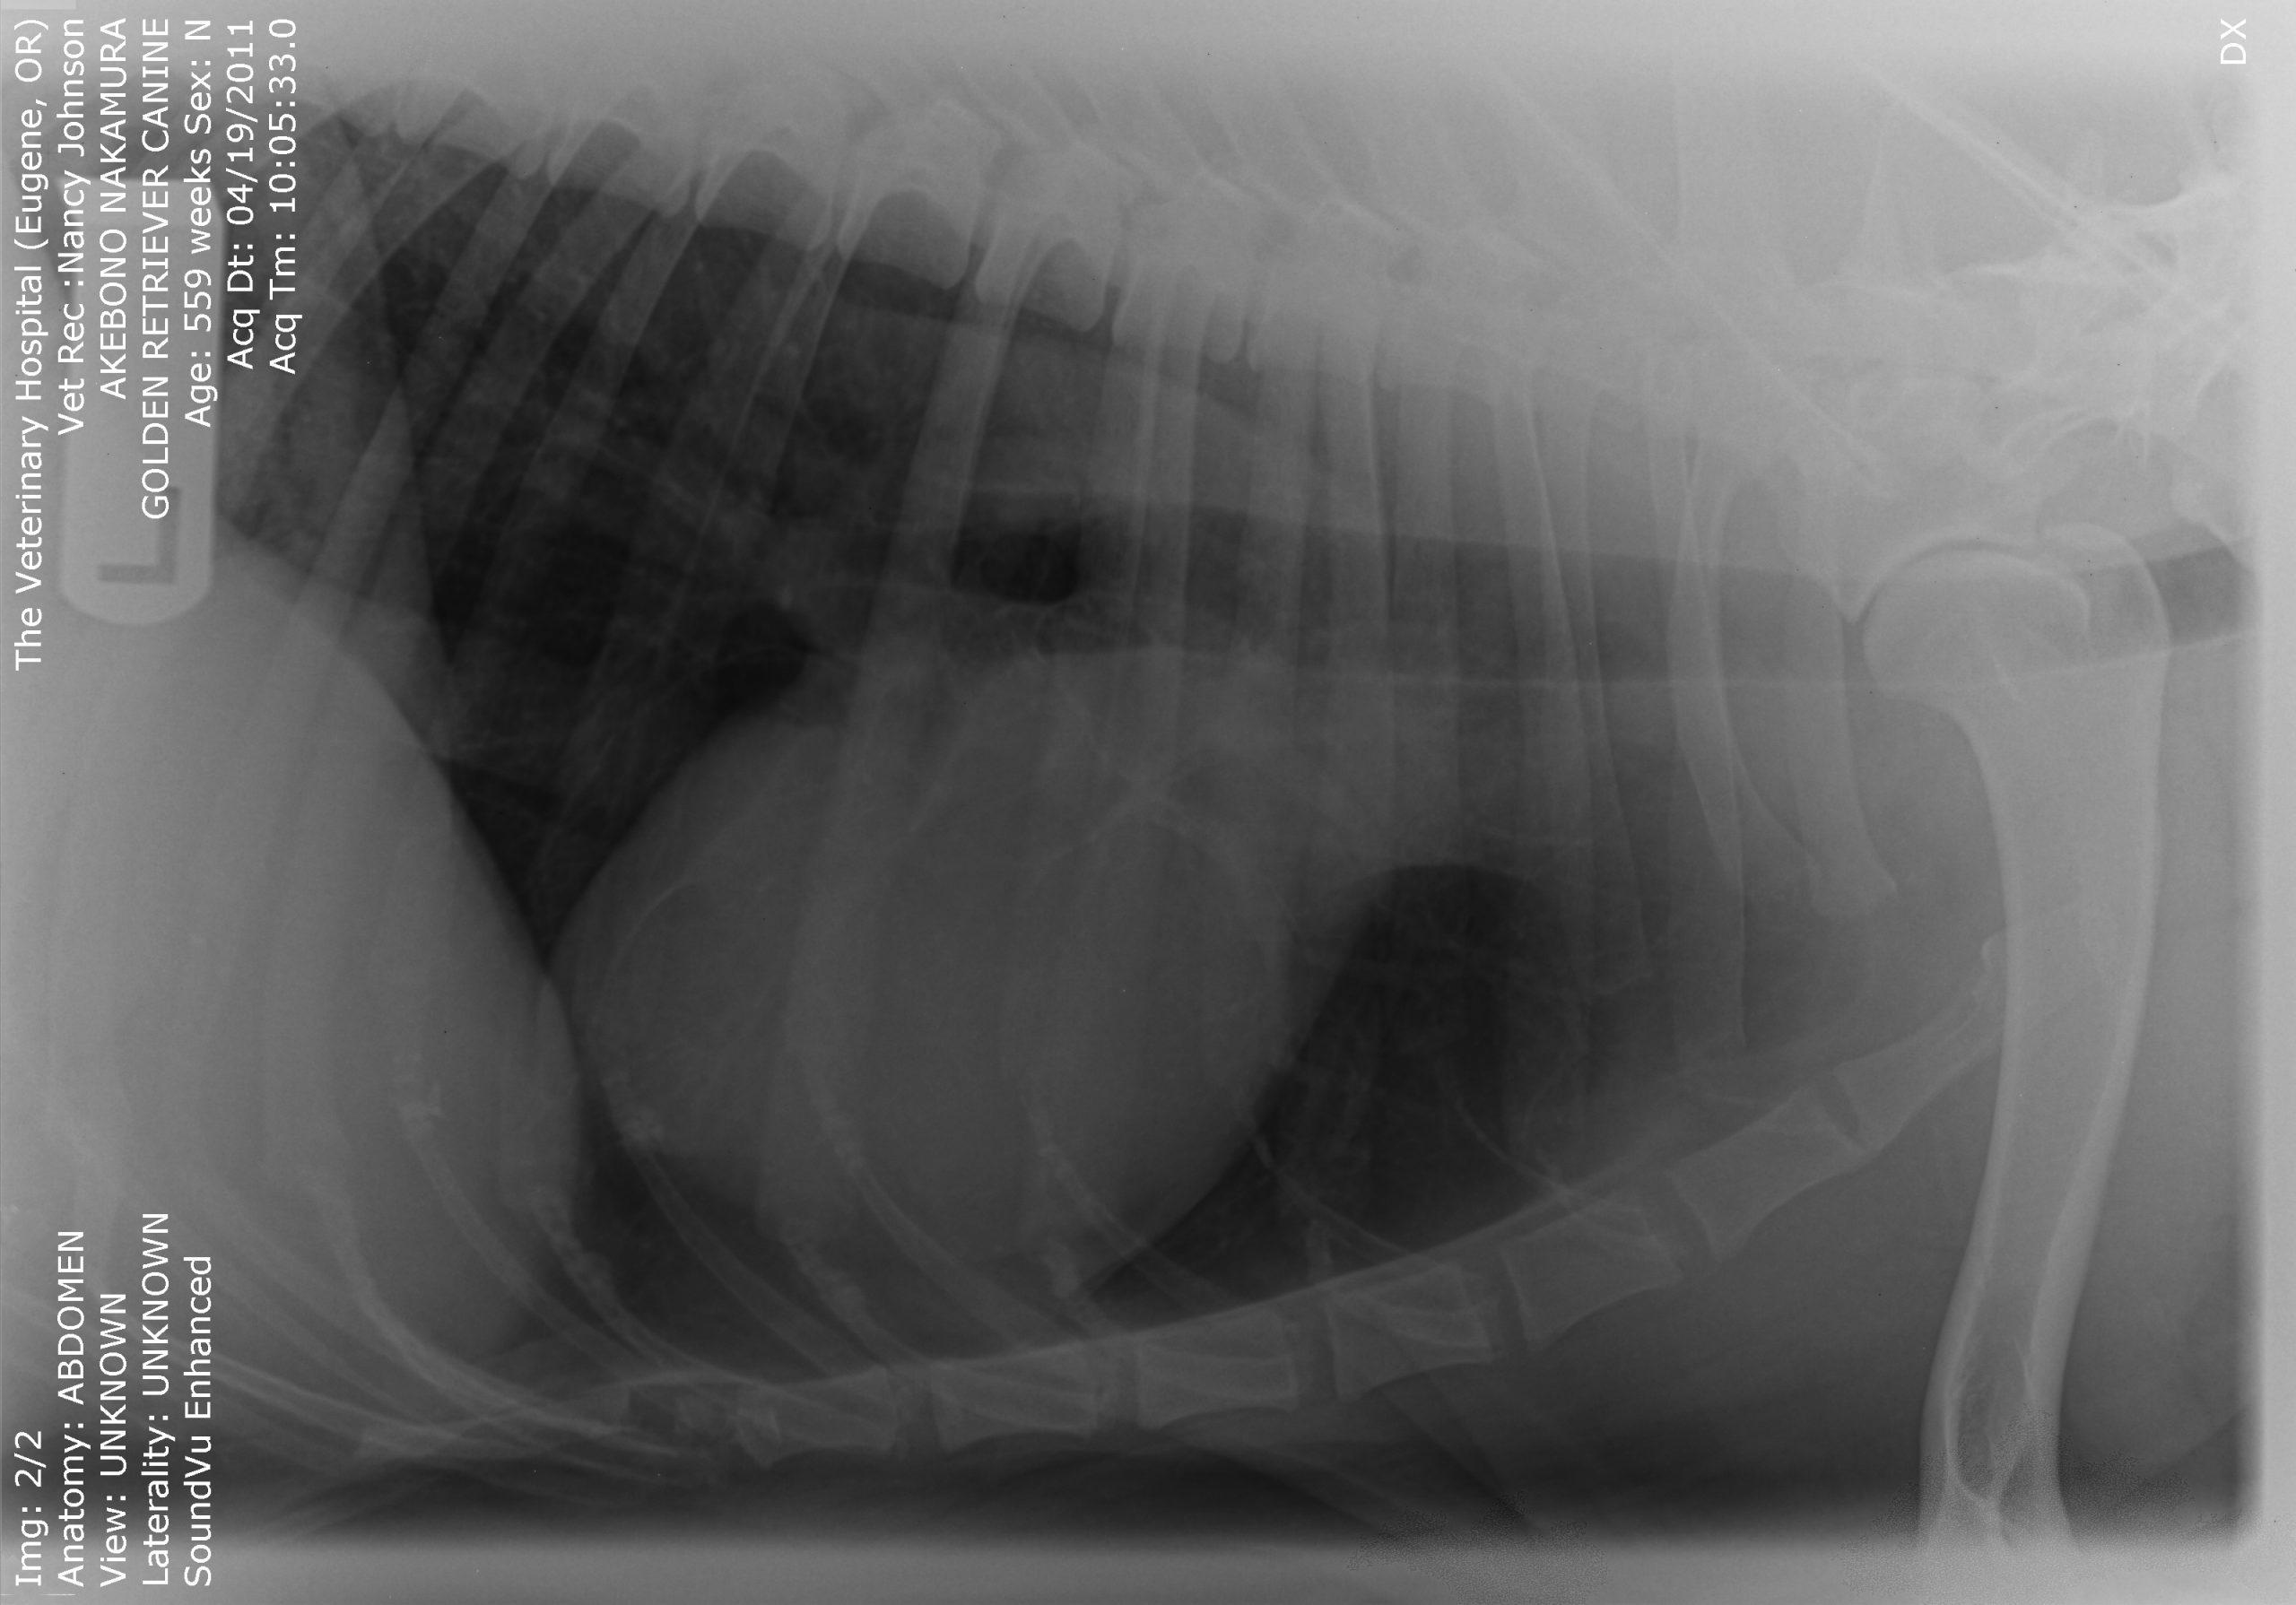

An 11-year-old MN Golden retriever was presented for evaluation due to two episodes of collapse and cyanosis. Additional history was that the patient was more lethargic than usual. Cardiac auscultation did not reveal any abnormalities and blood pressure was normal. Survey radiographs showed a mildly enlarged cardiac silhouette (VHS 11), prominent right ventricle, normal left atrial, and a normal lung pattern.